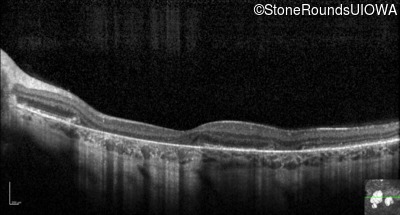

Optical Coherence Tomography - Right - 20/20 -2 sc

Exemplar / OCT Stack